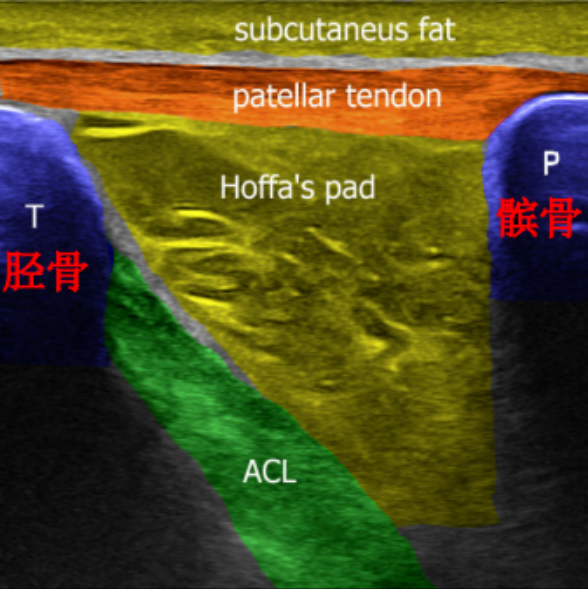

ACL 解剖

前交叉韧带起自股骨外侧髁的内侧面,斜向前下方,止于胫骨髁间隆起的前部。ACL 分为前内束(AM)和后外束(PL)。当屈膝 30° ~ 40° 时,前交叉韧带的张力最小。

6、关节超声

超声也可用于诊断前交叉韧带损伤其具有经济、快速和无痛的优点,但是其住确率较低目少须依靠经验丰富的超声医生。